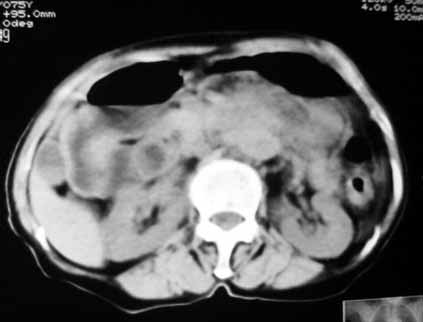

腹膜后软组织肿块,密度不均匀,病灶分叶,降主动脉受浸犯

考虑来源于腹膜后间叶组织的肿瘤

脂肪肉瘤,平滑肌肉瘤的可能性大

1.中腹部腹主动脉旁可见巨大包块影,其形态似为2个(或分叶),与腹主动脉分界不清,边界较清,其内密度不均匀(稍高、不匀称低密度),腹膜后未见确切肿大淋巴结...性质?考虑腹主动脉瘤可能性大,不排除平滑肌瘤及畸胎瘤可能,建议增强ct;

考虑:1、左侧腹膜后占位性病变(以间叶源性肿瘤可能性大);

脂肪肉瘤,平滑肌肉瘤的可能性大。支持!(本例关键是定位,仔细分析,可以观察到主动脉被包埋于肿瘤内,因此可定位于—来源于腹膜后的实性肿瘤。)

腹膜后肿块侵犯腹主动脉及肠系膜上动脉,肿块密度不均,1来源间叶组织肿瘤,2肠系膜恶性肿瘤可能大,

,因为如果是来源于腹主动脉的动脉瘤的话,长径应该呈梭形.腹主动脉被肿块包埋,考虑来源于小网膜囊的间质瘤